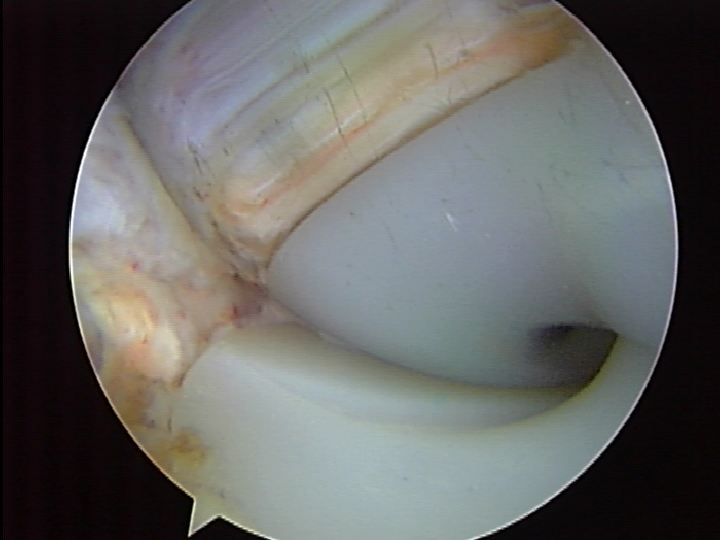

Pictures 1-2 show the injured PCL with a buckled ACL indicative of posterior laxity

- Picture 1

- Picture 2